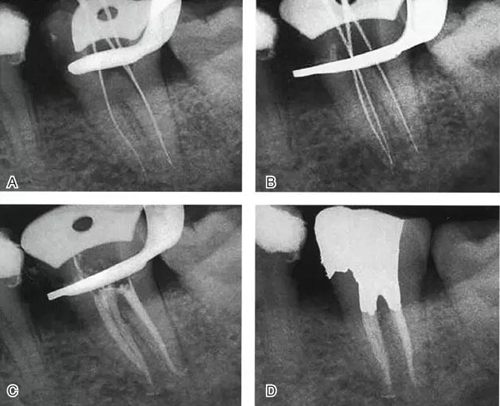

根管充填是C形根管治療成功與否的最重要因素。充填C形根管系統(tǒng)時,近舌及遠中根管可以進行常規(guī)充填。關(guān)于狹區(qū)的充填,更適合以熱牙膠垂直加壓充填,這種方法可使牙膠到達根管系統(tǒng)的每一死角(圖4~7)。

圖6 Ⅱ型C形根管治療典型病例,A:初尖銼片,B:主尖銼片,C:根充片,D:術(shù)后片

圖7 Ⅲ型C形根管治療典型病例,A:初始片,B:初尖銼片,C:主尖銼片,D:充填片